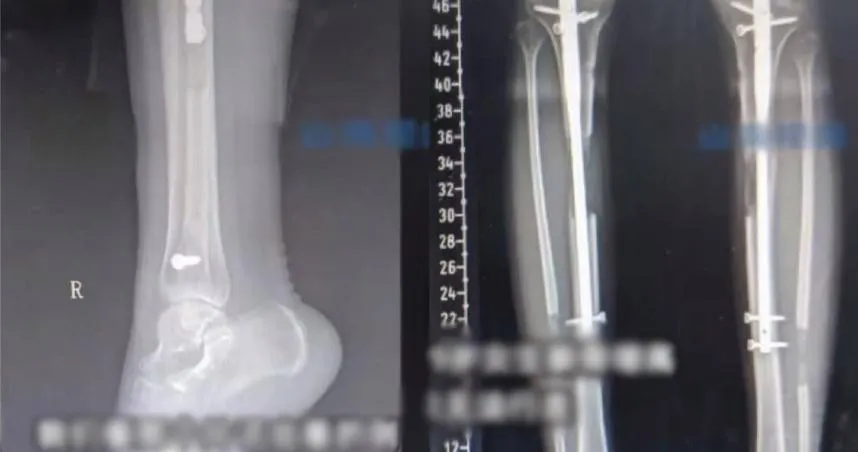

骨折

骨頭

手指骨折

骨頭斷掉